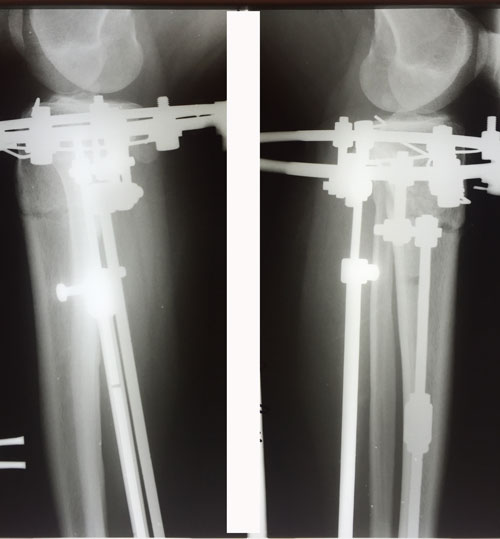

рентген в 55 дней с момента операции.

Сращение идёт отлично, снятие аппаратов планируется через 3 недели.